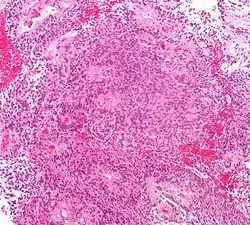

Micrograph of an ependymoma. H&E stain.

Ependymomas are composed of cells with regular, round to oval nuclei. There is a variably dense fibrillary background. Tumor cells may form gland-like round or elongated structures that resemble the embryologic ependymal canal, with long, delicate processes extending into the lumen; more frequently present are perivascular pseudorosettes in which tumor cells are arranged around vessels with an intervening zone consisting of thin ependymal processes directed toward the wall of the vessel.[5]